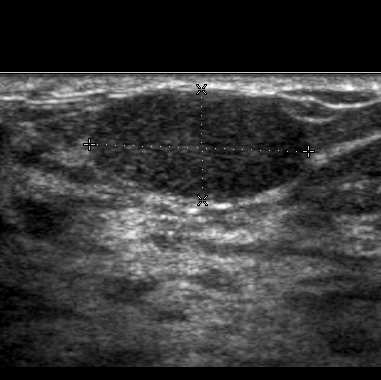

Drüsenkörper: ACR-Kategorie 2